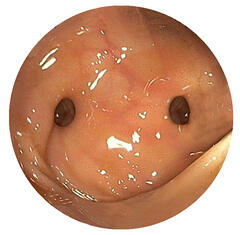

Eine Magen- oder Darmblutung ist ein häufiges Krankheitsbild. Meist blutet es im oberen Verdauungstrakt, d.h. im Magen, in der Speiseröhre oder im Zwölffingerdarm, es kann aber genauso im restlichen Dünndarm oder Dickdarm bluten. Die Ursachen sind sehr vielfältig – Magengeschwüre, Krampfadern der Speiseröhre, Krebserkrankungen, Entzündungen oder auch Gefäßveränderungen sind beispielsweise möglich. Abhängig von der Lokalisation und der Verweildauer des Blutes im Magen-Darm-Trakt, kann es z.B. zum Erbrechen von Frischblut oder zum Absetzen von schwarzgefärbtem Stuhlgang kommen. Eine stationäre Aufnahme ist meistens angebracht. Falls nötig kann der Kreislauf stabilisiert werden. Mittels Magendarmspiegelung kann die Blutung meist gut lokalisiert und behandelt werden.

Bei der Colitis ulcerosa beginnt die Erkrankung meist im Enddarm und breitet sich im Dickdarm aus. Blutig-schleimige Durchfälle, Bauchschmerzen, Fieber und erhöhte Entzündungswerte können auftreten. Meist kann mithilfe einer Darmspiegelung das typische Befallsmuster bestätigt werden. Neben medikamentöser Therapie kann bei Auftreten von Krebsvorstufen, schweren Schüben oder anderen Komplikationen eine chirurgische Dickdarmentfernung durchgeführt werden, durch die die Erkrankung geheilt werden kann.

Bei der Endoskopie kann mithilfe eines Endoskops der Magen-Darm-Trakt, die Gallengänge oder auch die Lunge angeschaut und beurteilt werden. Ein Endoskop ist ein lenkbarer, dünner Schlauch mit einer kleinen Kamera an der Gerätspitze. Des weiteren können mithilfe eines Endoskops auch Gewebeproben (Biopsien) oder Tumorvorstufen wie z.B. Polypen entnommen werden. Für die gesamte Untersuchung wird eine Sedierung angeboten, wodurch der Patient in einem Art Dämmerschlaf ist. Zum Spektrum der Abteilung gehört genauso auch die Ultraschalluntersuchung von außen (Sonographie) und von innen (Endosonographie) dazu – mit der Möglichkeit, Gewebeproben zu entnehmen.